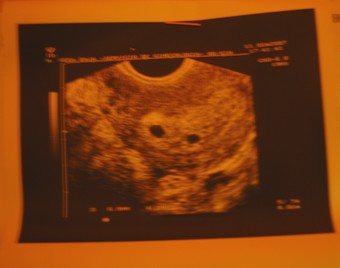

Sziasztok Lanyok, ezer bocs hogy nem irok MEG VAGYOK IJEDVE!

Voltunk uh-on az ugyeleten mert kicsit barnaztam erre:

Kép

Ket petezsak van de csak az egyikben latszik embrio a masikban semmi lehet hogy elhal de az is lehet hogy kesobbi baba! Szerintetek lehet hogy O is fejlodesnek indul? Volt valakinek ilyen tapasztalata? Ugy tudom gyakori az ilyen es nagyon sokszor az egyik baba felszivodik.